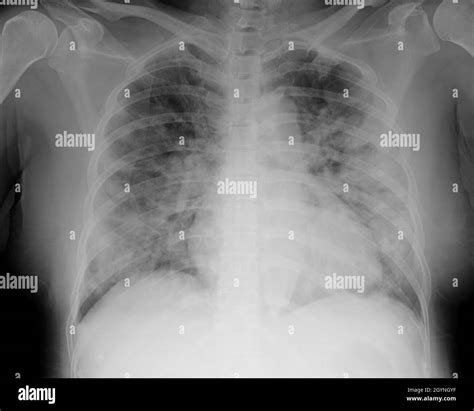

A Pneumonia X-ray is a medical imaging test that uses electromagnetic radiation to create pictures of the inside of your chest. When you have pneumonia, the air sacs (alveoli) in your lungs can become filled with fluid or pus. In an X-ray image, these filled air sacs appear as opaque, whitish patches or "opacities," which stand out against the dark, air-filled healthy lung tissue. This visual evidence is critical for doctors to distinguish pneumonia from other conditions like bronchitis or asthma.

When a radiologist reviews a Pneumonia X-ray, they are looking for specific indicators of disease. Healthy lungs on an X-ray typically appear black because they are filled with air, which does not block the X-ray beams. Conversely, infected tissue blocks these beams, leading to white areas on the film. These findings are often referred to in clinical reports as "infiltrates" or "consolidation."

Clear black lung fields Healthy, air-filled lungs

Localized white patches (Consolidation) Indicative of active pneumonia infection

Cloudy shadows Possible interstitial inflammation or fluid

Blunted costophrenic angles Potential sign of pleural effusion (complication)